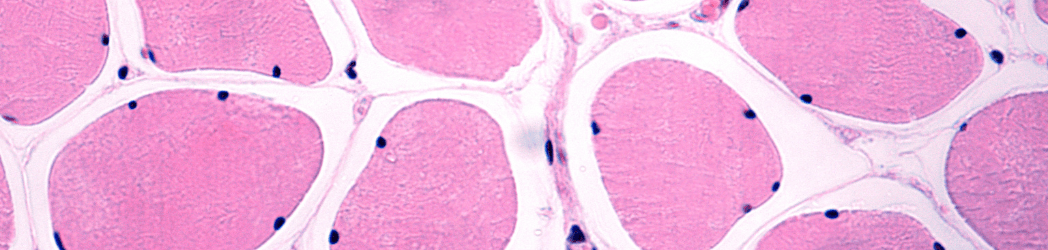

In cross-section, healthy skeletal muscle fibers are tightly packed and form a tessellation, with each fiber taking the approximate shape of a pentagon or hexagon. However, as a muscle fiber atrophies, it tends to take on a more complex and often elongated shape in cross-section. One of the ways to quantify the irregularities in shape is with a “shape factor index” (SFI), which calculates the ratio of the fiber’s perimeter to the fiber’s cross-sectional area. The SFI of a perfect circle is one, whereas an oval with the same area as the circle will have an SFI greater than one. This metric quantifies the deformity of the shape of muscle fibers in cross-section (with higher numbers corresponding to greater deformity) but does not account for the overall size of the fiber (see panel A in the Figure below). Instead, the SFI distinguishes two fibers of similar cross-sectional areas with different levels of deformity (see panels B and C).

In the evaluation of the muscle biopsies, mean SFI exhibited a significant increase across increasing age groups for both type I and type II muscle fibers, demonstrating that the measurement of myofiber shape distortion increases with advancing age, regardless of muscle fiber type. However, the age-related increase in SFI was greater in type II fibers than in type I fibers, and the mean SFI was higher in type II fibers than in type I fibers across all age groups, implying that the type II variety are even more susceptible to atrophy and deformity across an individual’s lifespan than type I fibers. Indeed, compared to the young group, the old and oldest-old groups respectively had a 6.2% and 13.6% higher SFI in type II muscle fibers. Additionally, type II fiber SFI was an independent predictor of overall muscle size (as measured by the cross-sectional area of the quadriceps) and muscle strength (as measured by isometric and isokinetic maximal voluntary contractions).